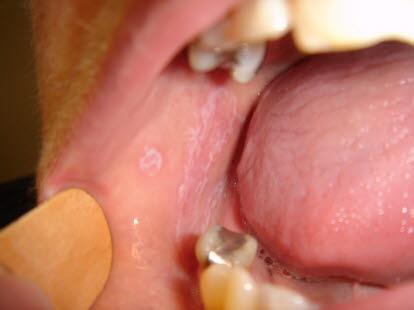

Slimhinneforandringene i munnhulen kan ha litt ulike utseender. Det kan være som et mønster av tråder og nett (retikulær form), det kan være partier som kun er røde (erytematøs form), eller det kan være sårdannelser (erosiv form). Den retikulære formen er lettest å se, den gir ofte lite plager, men den kan være sjenerende når den finnes på tungen. Den erosive formen er den mest plagsomme.